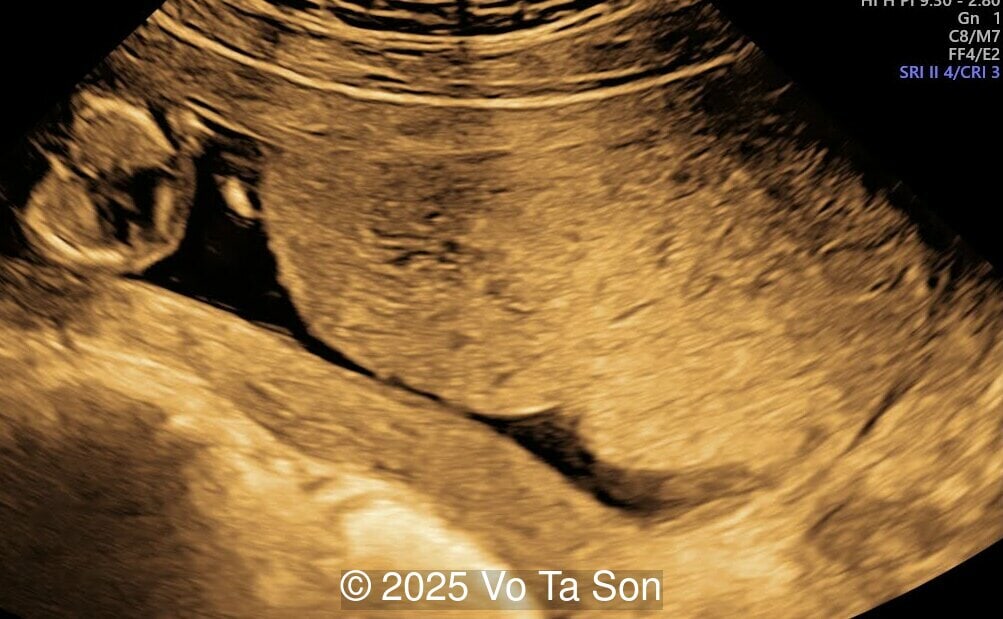

A primary spinal lesion is observed in the sacral region, characterized by a posterior vertebral arch defect and a protruding meningeal sac.

Image 1 A primary spinal lesion is observed in the sacral region, characterized by a posterior vertebral arch defect and a protruding meningeal sac.

Spinal defect in the sacral region visualized on 3D ultrasound.

Image 3 Spinal defect in the sacral region visualized on 3D ultrasound.